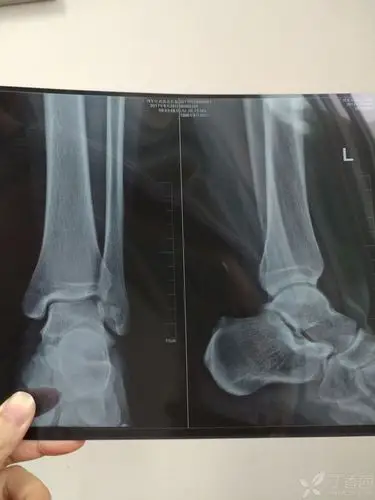

x14180右踝关节扭伤外踝痛请教各位老师

请骨科战友帮忙看一下左踝关节x线片 [病例帖]

左侧踝关节外伤x光